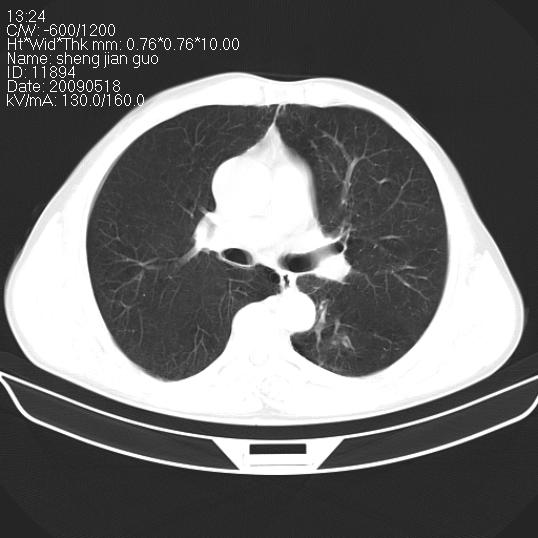

以下是引用zjzjr在2009-5-19 17:25:00的发言:[br]支持楼主考虑,另左肺下叶阻塞性炎症。

以下是引用zhao_bin2008在2009-5-19 17:48:00的发言:[br]支持左肺下叶周围型肺癌并阻塞性肺炎。

以下是引用zsl6918在2009-5-20 7:10:00的发言:[br]左侧中心型肺癌!